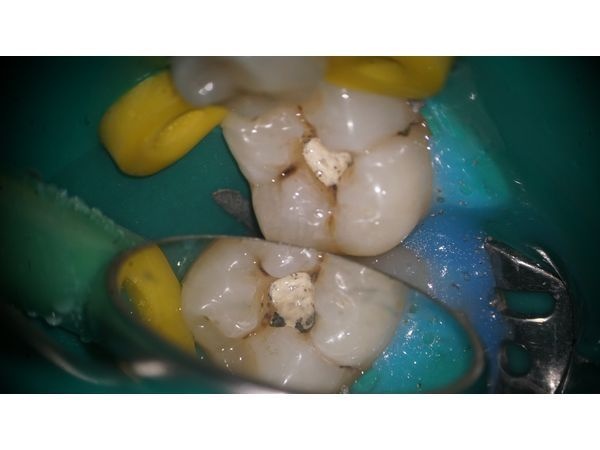

- установили постоянную пломбу из светоотверждаемого композита с учётом анатомии зуба;

- проверили и откорректировали реставрацию по прикусу, отполировали;

Все этапы лечения фиксировали с помощью камеры. После манипуляции пациентке показали фотопротокол и объяснили выполненные действия.